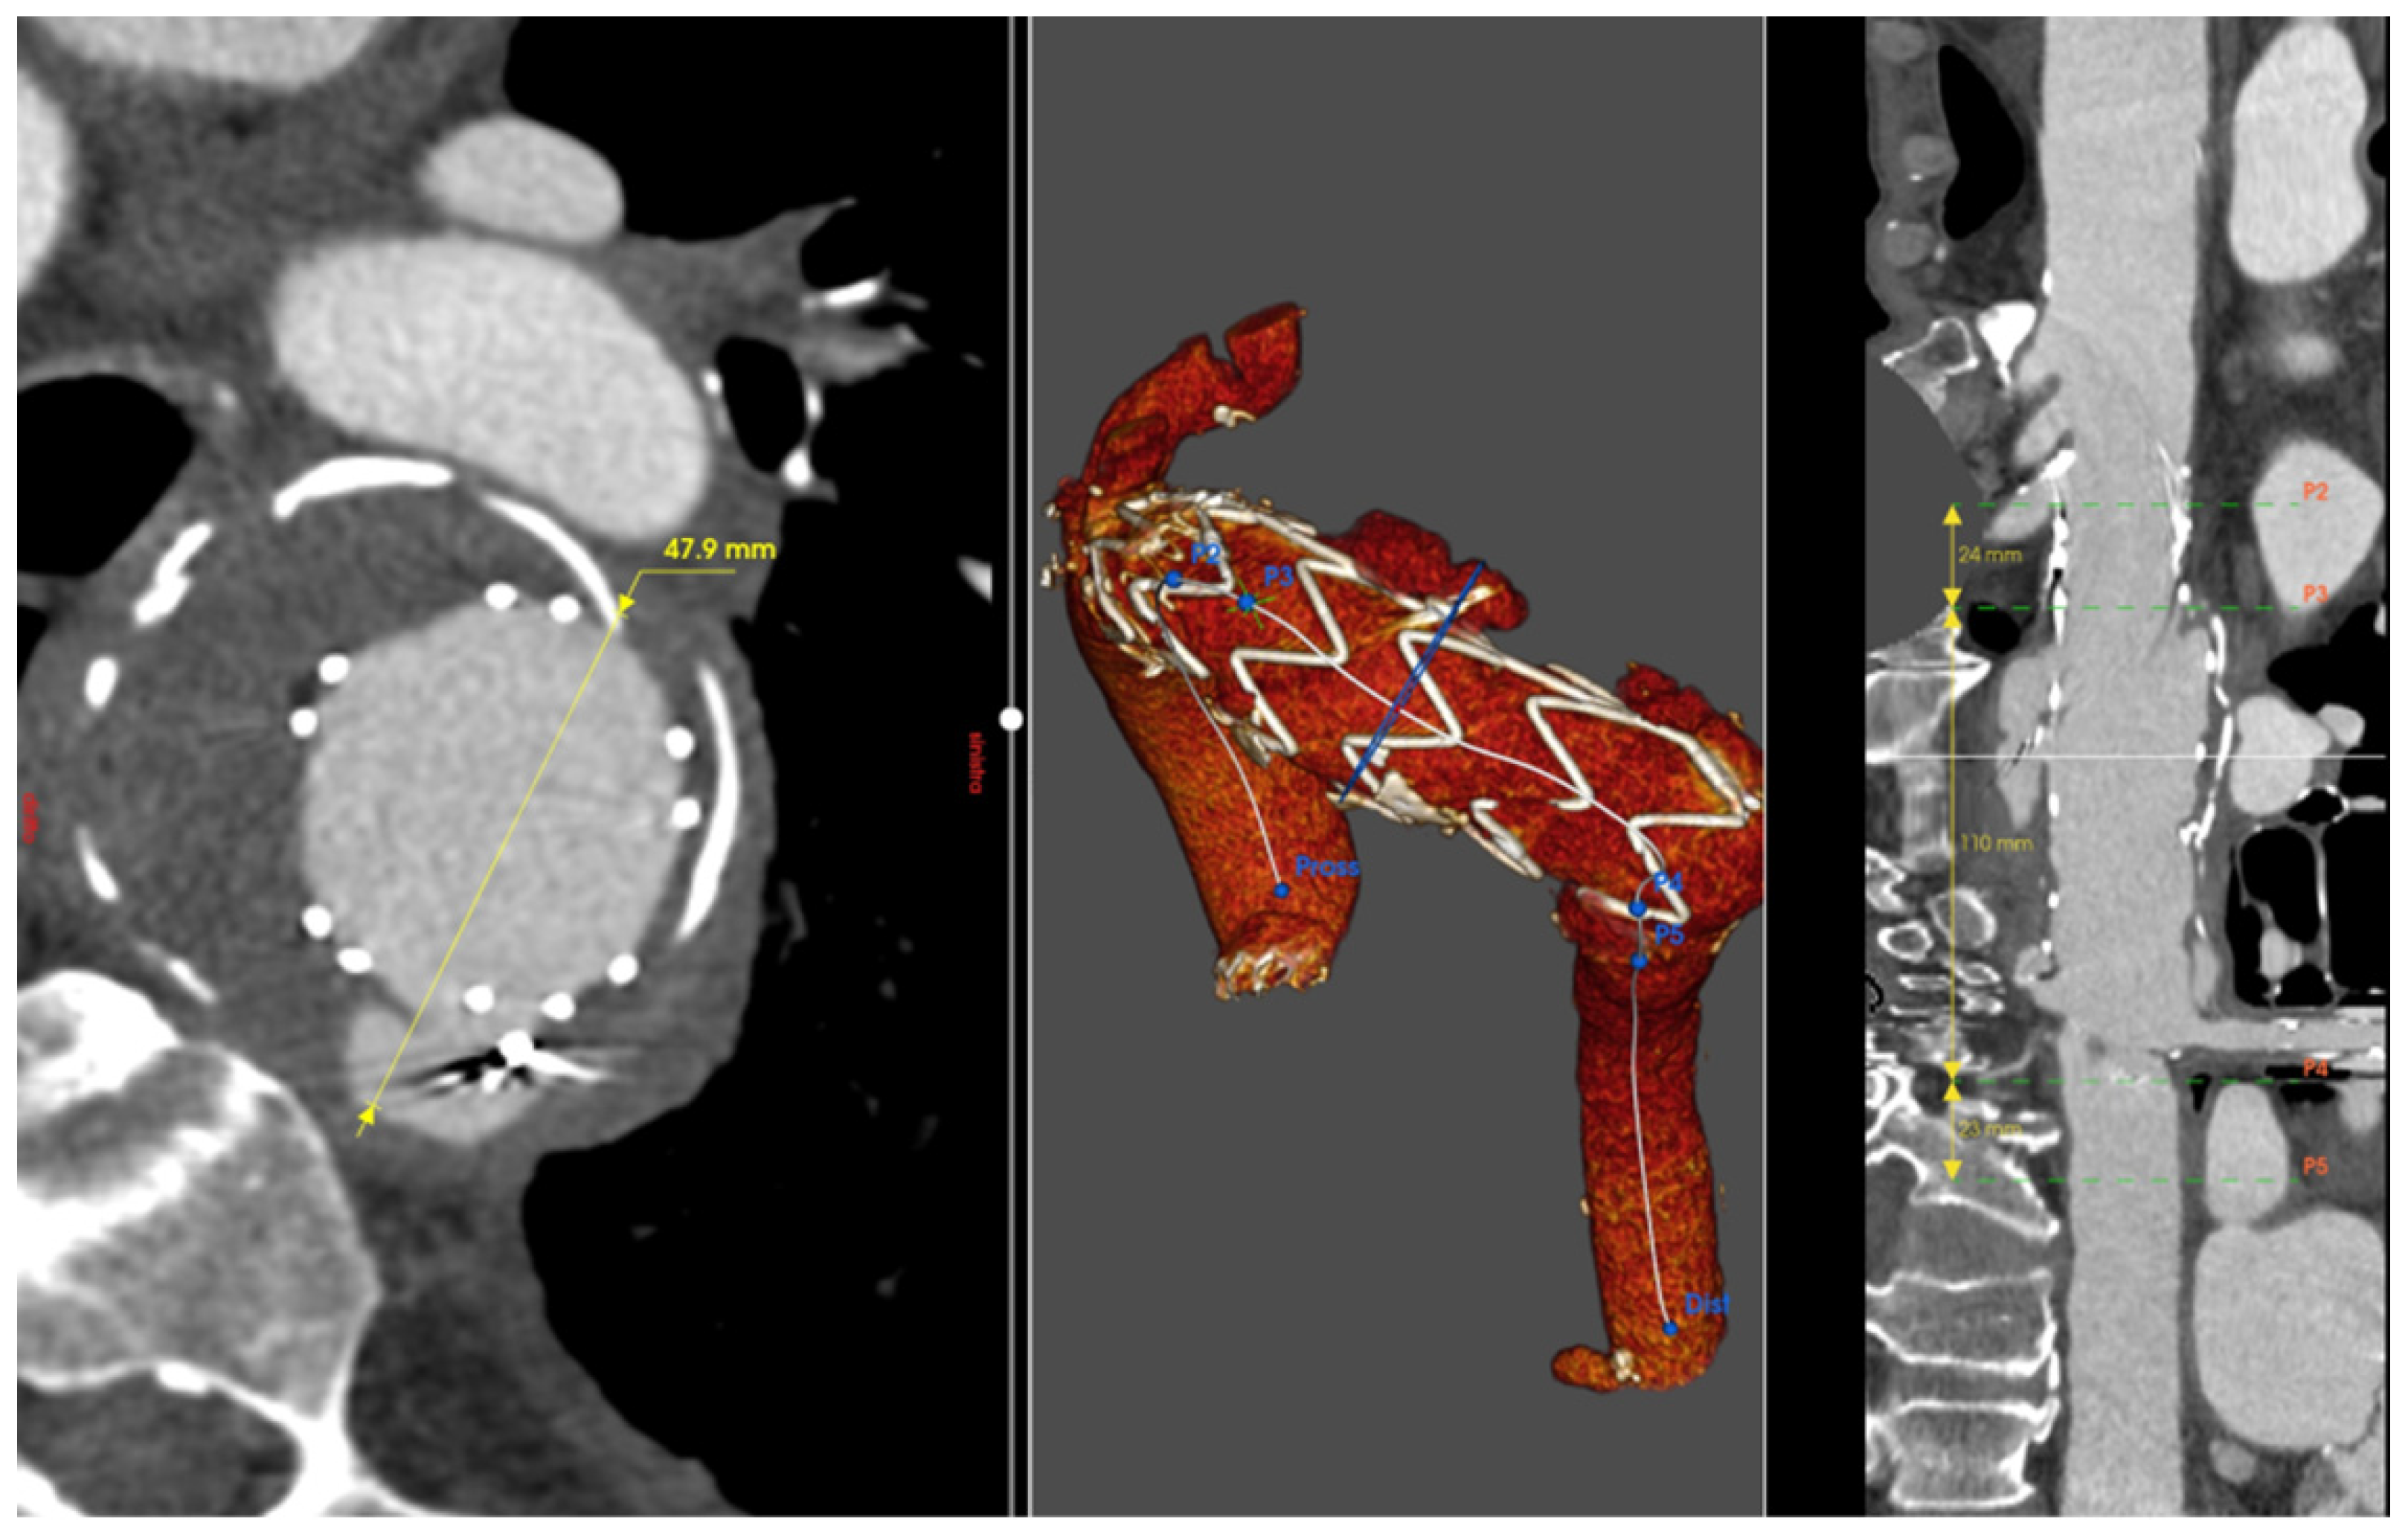

2.1. Patient 1

2.2. Patient 2

2.3. Patient 3

2.4. Patient 4

2.5. Patient 5